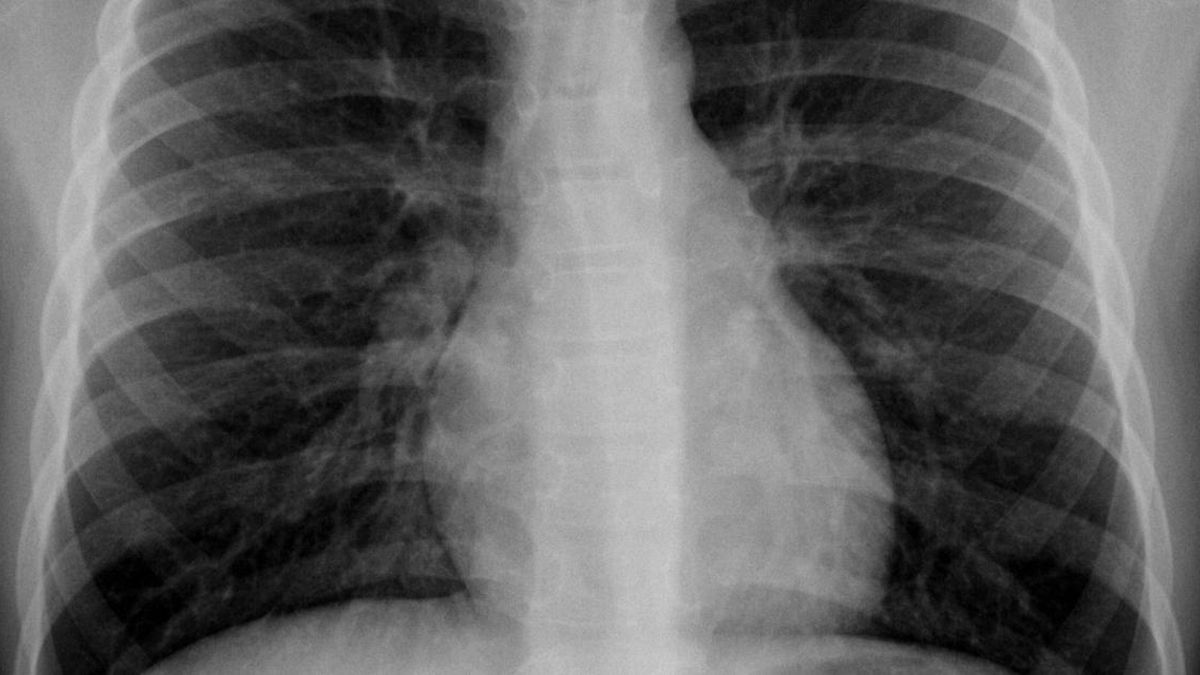

Según el informe médico, el esputo de mujer, una maestra de la escuela, fue examinado para detectar tuberculosis pero resultó negativo. Sin embargo, cuando le escanearon el pecho a través de una radiografía, encontraron una lesión en el lóbulo superior derecho de sus pulmones.

Tras una mayor investigación, parecía ser "una estructura en forma de bolsa invertida asentada en el bronquio". Los especialistas extrajeron la misteriosa "bolsa". Y pese a que la mayor parte fue destruida por el proceso, se pudo identificar que era un preservativo.